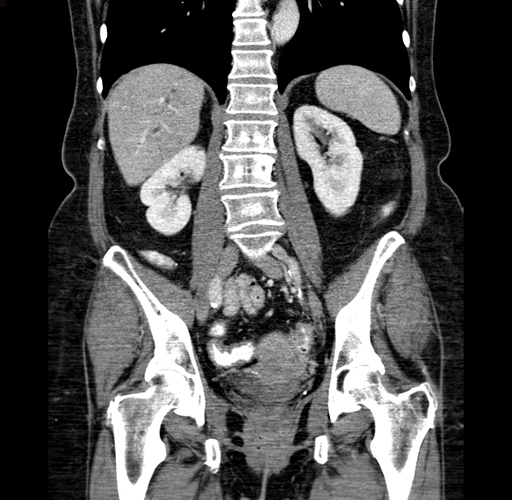

Pre-Chemo: Coronal Venous

Coronal Venous